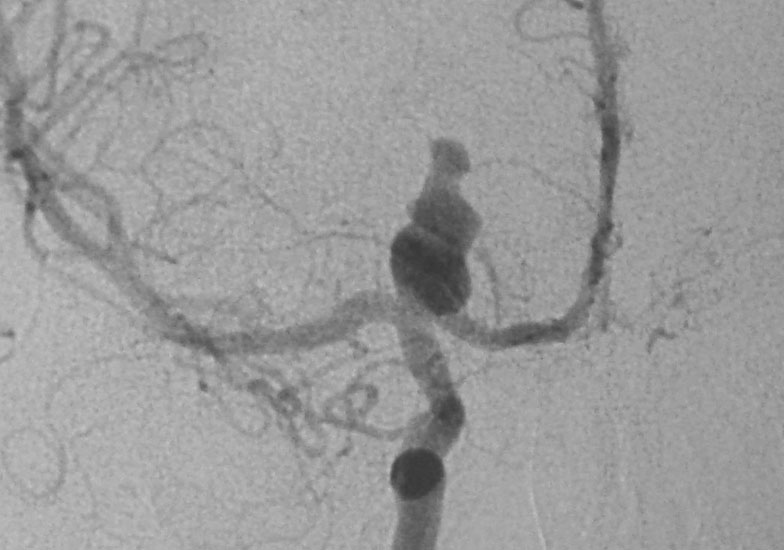

ICA Bifurcation Aneurysm

A 38-year-old-male was admitted with sudden onset of severe global headache and vomiting, followed by altereation in sensorium. CT brain showed subarachnoid and intraventricular hemorrhage (Fig 1). MRI brain revealed deep seated right sided thalamic hematoma due to ruptured internal carotid artery bifurcation aneurysm (Fig 2), confirmed by cerebral digital subtraction angiography (Fig 3). He underwent clipping of the aneurysm by transciliary supraorbital keyhole minicraniotomy (see video). Postoperative angiography showed complete occlusion of the aneurysm (Fig 4). When discharged ten days later, there was no neurological deficit (Fig 5).

Fig 3

(Fig 3)